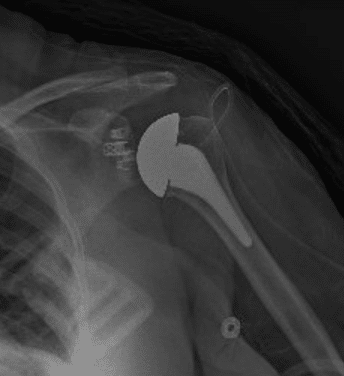

BH is a right hand dominant 70-year-old female, who is retired and moderately active. She presents with 8 months of progressively worsening left shoulder pain affecting her ADLS, sleep and recreational activities. She is 10 years s/p a right anatomic total shoulder arthroplasty. Radiographs and advanced imaging reveal glenohumeral joint advanced degenerative joint disease with an intact rotator cuff. Preoperative planning reveals a native 3 degrees of retroversion with 0 degrees of inclination. As she was extremely happy with the fully functional contralateral shoulder she has enjoyed for the past decade, she was interested in the same solution – an anatomic total shoulder arthroplasty.

At age 70 secondary rotator cuff tears following anatomic total shoulder arthroplasty must be weighed against complications and postoperative function of reverse shoulder arthroplasty [3]. Advita Predict+ was able to demonstrate comparable postoperative function, scores, pain, and complications. A decision was reached to proceed successfully with an anatomic total shoulder arthroplasty.